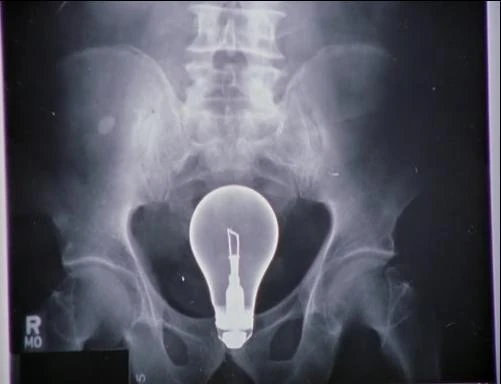

Unglücklicherweise müssen sich die beiden ein gemeinsames Büro teilen, das ungefähr die Größe einer Besenkammer hat. Da die beiden nicht mehr befreundet sind, seitdem J.D. Elliot verlassen hat, haben sie 2 Optionen, wie sie die Sache regeln können: 1. Sie verhalten sich wie Erwachsene oder 2. wie Kinder. Da die zwei Chief Residents letzteres bevorzugten, laufen sie nur noch getrennt durchs Gebäude, um einander aus dem Weg zu gehen. Doch als ein Patient plötzlich im Sterben liegt beenden sie die Kindereien und helfen zusammen. Später sitzen die beiden in der Cafetatria und erinnern sich warum sie mal so eng befreundet waren Währenddessen muss Dr. Cox im Auftrag von Dr. Kelso den Sohn eines Aufsichtsratsmitglied behandeln, der eine Glühbirne in seinem Hintern hat. Ein schwieriger Fall, da die Glühbirne sehr zerbrechlich ist. Molly, die neue Psychiaterin, hingegen fertigt inzwischen eine Studie an, in der es um Konfliktsituationen im Krankenhaus geht. Ihre Hauptperson ist dabei Dr. Cox, der durch ein paar Diagnosen mit Turk in Konflikt gerät. Als der zynische Oberarzt jedoch Hilfe von ein paar anderen Leuten braucht, um "die Glühbirne aus dem Arsch des Genies zu kriegen", kommt Turk gerade Recht.

• Der Hausmeister hilft Turk und Dr. Cox durch sein Wissen über Glühbirnen, den Patienten richtig zu behandeln und prahlt mit seinem Fachwissen über verschiedene Glühbirnenmodelle.